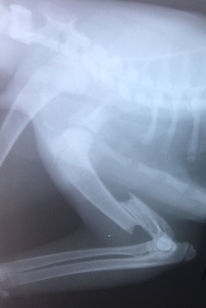

Переломы плечевой кости

Перелом плечевой кости: диафизарный, не оскольчатый, со смещением, закрытый. Слева - прямой. Справа - косой. Выполнен комбинированный остеосинтез: интрамедулярный и внеочаговый, с помощью ретроградной спицы и аппарата внешней фиксации.

Восстановление опоры: 7 день после операции. Прогноз: благоприятный